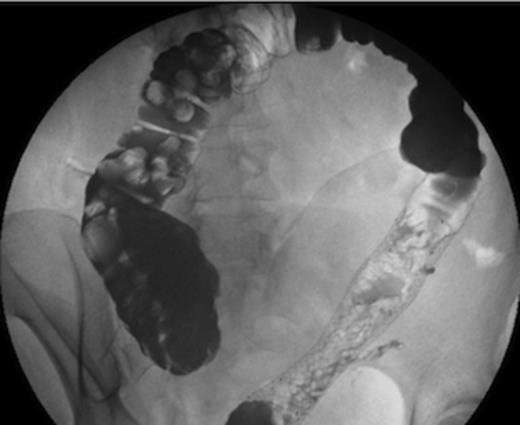

At a clinic review two months post Hartmann’s reversal, the patient complained of intermittent discharge from the lower end of her laparotomy wound associated with per-rectal intermittent discharge of mucous and blood. Contrast Studies had revealed the presence of an anastomotic stricture complicated with a colo-cutaneous fistula (Figure 1).